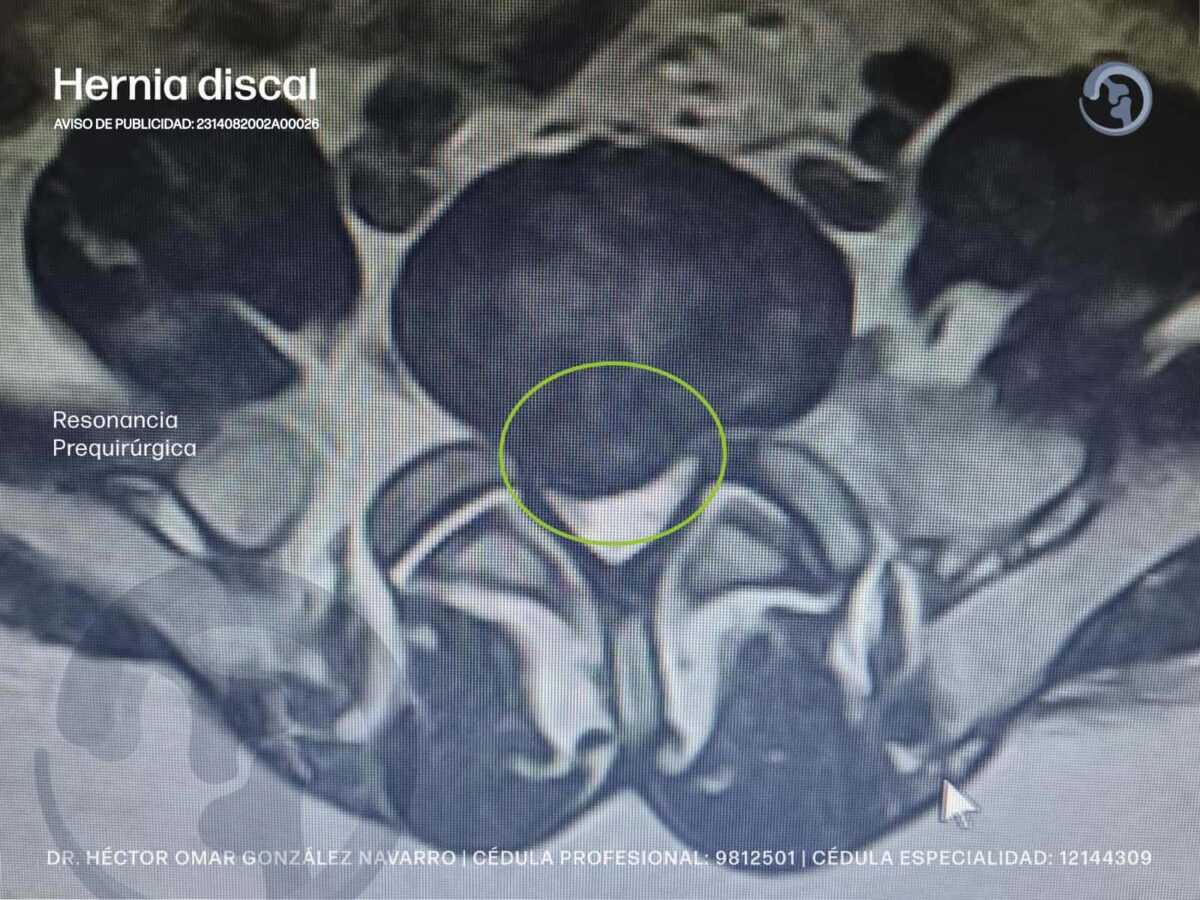

¿Sabías que la columna vertebral puede presentar hernias? Particularmente hernias de disco. Las vértebras se encuentran separadas entre sí por un disco intervertebral. Estos discos tienen la función de absorber el impacto al caminar, saltar y brindar estabilidad, sin embargo si se desliza de su posición se conoce como hernia discal, disco herniado, deslizado o roto.

Abordaje quirúrgico de las hernias de disco

Si no hay mejoría con el tratamiento conservador, o los síntomas son graves, se recurre al tratamiento quirúrgico. El objetivo es mejorar la calidad de vida de las personas, ya que la progresión de los síntomas puede dificultar o interrumpir las actividades diarias. Si el disco herniado comprime todo el canal medular, puede causar incontinencia, dificultad para orinar y disfunción intestinal, así como pérdida de sensibilidad y/o fuerza en las extremidades superiores o inferiores.

Cada caso es individualizado pero por lo general, Se realiza en un quirófano y el objetivo es retirar parte del disco herniado o extraerlo por completo, en ocasiones se sustituye con un implante entre las vértebras afectadas, o en algunos casos es necesario retirar una porción del hueso para liberar la compresión del nervio. Esto determinará si se recurre a técnicas abiertas o por mínima invasión.